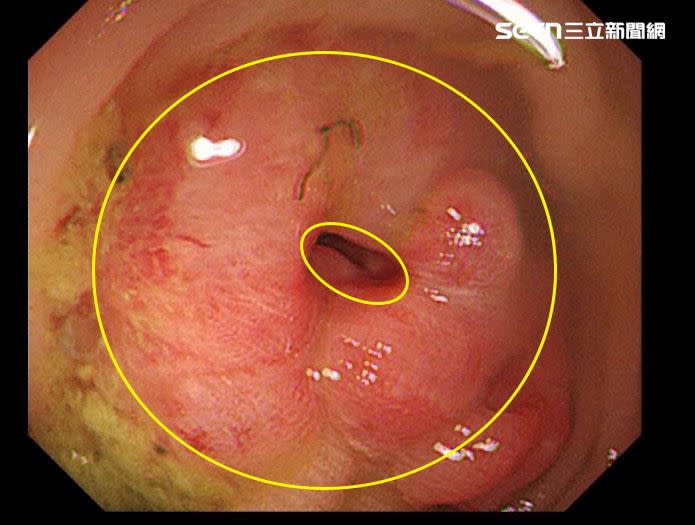

27岁男硕士生平时吃素,因爱吃加工品、精致淀粉与高温油炸食物,罹患直肠癌并出现淋巴结转移。(图/翻摄画面)

陈周诚医师分享,临床上病患常有错误观念,以为吃素就不会得到大肠直肠癌,但不良饮食习惯不分荤素。以27岁的男硕士生为例,患者平时吃素,但爱吃加工品、精致淀粉与高温油炸食物,最终罹患直肠癌合并肠道部分阻塞,出现淋巴结转移。经手术治疗后,目前使用标靶药物及化疗保命。